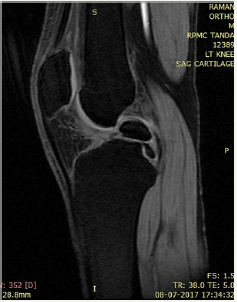

Figure 2: STIR.

Figure 3: Sagittal STIR.

We present a case of 14 year old male child who had history of pain in the right knee while climbing upstairs for long duration. There was no history of any significant trauma in the past. After clinical examination by the orthopaedician in the outpatient department patient came to our department for MRI right knee with strong clinical suspicion of ACL injury. We did MRI of right of the patient and found a large ossicle intra-articularly which was impinging the ACL. The ossicle showed the signal intensity of bone on all pulse sequences. No other pathology was noted in the right knee joint (Figure 1-5).